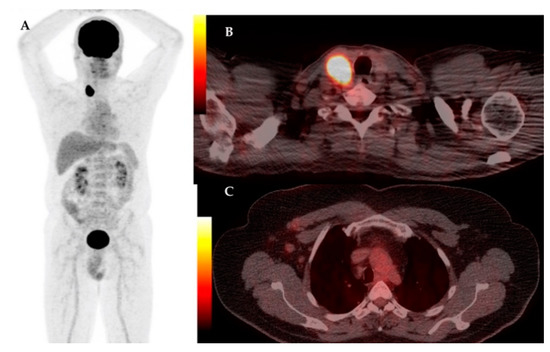

| 5 | 70 | IDC | RM + ALND | – | – | IB | – | Lu, Su | 3.37 | Colon cancer | 5.27 |

| 11 | 47 | IDC | RM + ALND | – | – | IIB | – | LN, Bn | 10.61 | – | – |